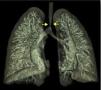

Um rapaz com 2,5 anos apresentou estridor bifásico aos três meses, que agravava com o choro, alimentação e infeções respiratórias altas. Realizou broncofibroscopia (BF) aos cinco meses que diagnosticou traqueomalácia com colapso dinâmico de 80% nos 2/3 inferiores da traqueia. Crescimento normal e sem dificuldade alimentar. Por estridor persistente, a BF aos 21 meses visualizou colapso dinâmico marcado e compressão extrínseca da traqueia. Realizou angiografia por tomografia computorizada (angio‐TC) do tórax, que identificou anel vascular formado por duplo arco aórtico (Figuras 1‐3) responsável por compressão extrínseca sobre a traqueia com franca redução segmentar do seu calibre (Figura 4). Sem outras malformações cardíacas no estudo ecocardiográfico. Aos 23 meses foi submetido a laqueação e divisão do arco mais hipoplásico (anterior esquerdo) por toracotomia. Boa evolução pós‐operatória, mantendo atualmente estridor ligeiro.

Os anéis vasculares representam 1% das cardiopatias congénitas e são a malformação congénita mais frequente com compressão da via aérea. Neste caso a manifestação clínica predominante orientou a sequência de exames de imagem – BF e TC. A combinação de imagens é fundamental na avaliação pré‐operatória. A angio‐TC apresenta vantagens como melhor resolução espacial e temporal, rapidez de aquisição de imagens exigindo apenas sedação/anestesia curta nos doentes não colaborantes, pós‐processamento de imagens com reconstruções tridimensionais e a redução da quantidade de radiação com os equipamentos recentes permite eleger este meio como o preferencial. A avaliação da traqueomalácia ou outro compromisso funcional da via aérea continua a exigir a realização de videobroncoscopia.